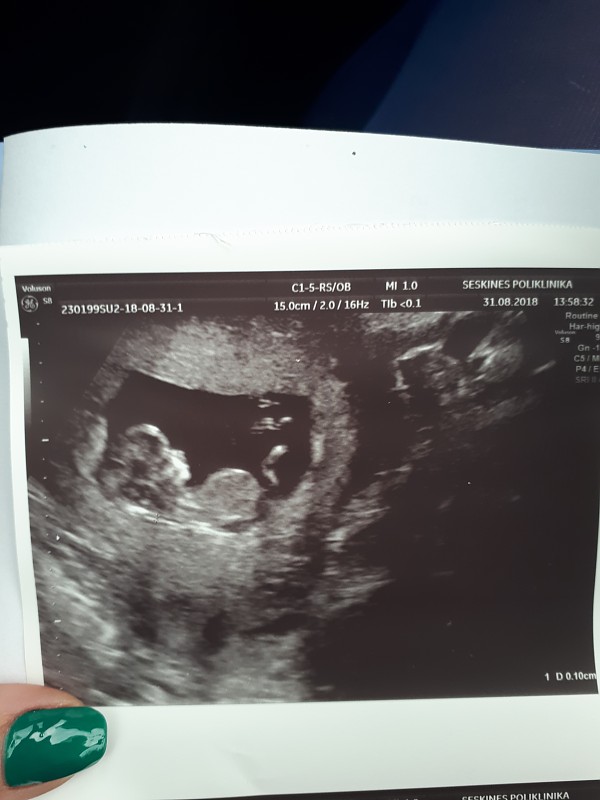

Norejau kurti nauja tema. Ja geriau butu pavadinti pagal NUB teorija.

sia teorija susidomejau gan atsitiktinai, kai vyrui pavyko pafilmuoti musu trecio …

Dazniausiai darant echo yra matomi du arba trys bruksneliai. Mums net nuotrauka dave su trim bruksniukais, nes geru kampu pagavo ir vualia ;) turim mergaite!

Na pagal nub teorija ne visai taip. nes pagal sia teorija nustatuneja lb anksti, nuo 12 sav. Ten reikalingas sagitalinis vaisiaus vaizdas (vaizdas is sono, isilgai stuburo) ir esme, kad vertinamas nub organas. kuris pas berniukus issivysto i peni, pas mergaites i klitoriu. Esme sio organo uzuomazgeles kampas ir dydis.

Is nuotraukos, kurias duoda gines, laaaabai retai, kada buna pagautas reikiamas kampas. Visai kas kita, kai ziuri nufilmuota irasa. Tada, galima 80-90 proc tikslumu atspeti. O is tokios nuotraukos tik burimas, kaip su ziedu